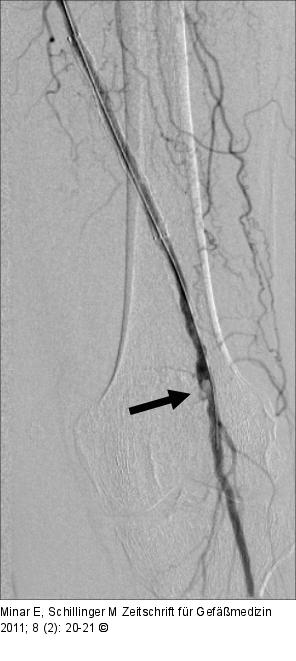

Abbildung 2: Ballonangioplastie

Kontrollangiographie nach Ballonangioplastie. |